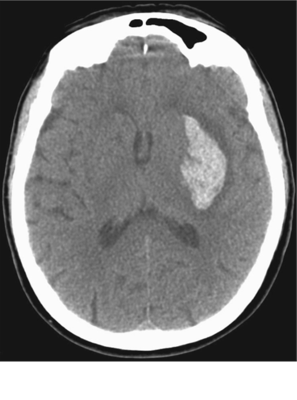

El siguiente tac sin medio de contraste(figura 370-17 de harrison 18 ed) nos muestra lo siguiente:

Answer

• Hemorragia por hipertensión del lado izquierdo.

• Hemorragia por aneurisma del lado derecho.

• Hemorragia por hipertensión del lado derecho.

• Hemorragia por aneurisma del lado izquierdo.